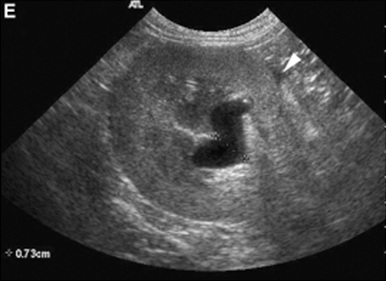

신우는 보통 보이지 않으나, trans view를 잘 잡으면 보일 수 있습니다(그림 2). 신우의 폭은 1-2mm로 무에코의 선으로 관찰됩니다. 수액 투여 시에는 일시적 확장이 있으며, 결석으로 인한 요도폐색, 종양, 이소성 요관이나 신우신염이 있을 때는 확장이 될 수 있습니다(Table 2, 그림 3). 또한 leptospirosis, 신장의 말기 상태나 신장이식 등에서도 나타날 수 있습니다3).